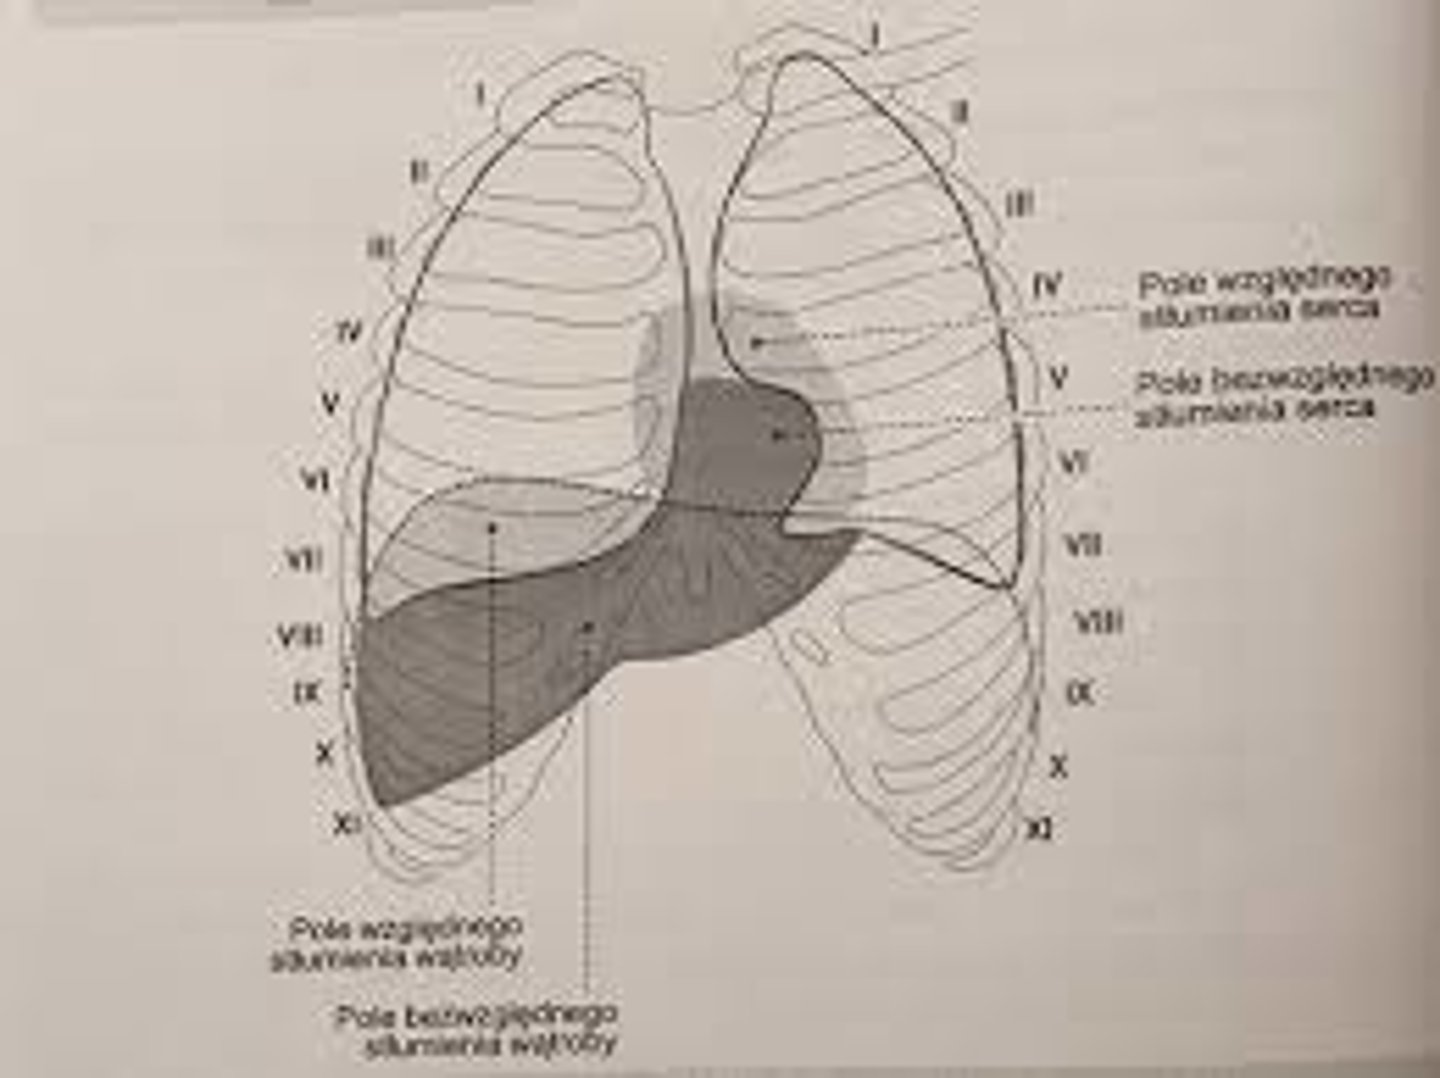

Jakie cechy można określić na podstawie opukiwania?

wielkość i kształt serca

Co wyróżnia się na podstawie różnic odgłosu opukowego?

stłumienie bezwzględne i względne

Co obejmuje pole bezwzględnego stłumienia?

u góry 4. przestrzeń międzyżebrową

od prawej brzeg przedni płuca prawego

od lewej wcięcie sercowe płuca lewego

od dołu nie da się określić granicy

Co obejmuje pole stłumienia względnego?

odpowiada obrysowi serca

górna granica: ku tyłowi od mostka na wysokości górnego brzegu żebra III

lewa granica: od górnego brzegu III żebra do miejsca uderzenia koniuszkowego w 5. przestrzeni międzyżebrowej

prawa granica: równolegle do prawego brzegu mostka

dolna granica: przechodzi w stłumienie wątroby -> brak stłumienia względnego

Jak biegnie lewy obrys serca?

od górnego brzegu III żebra do miejsca uderzenia koniuszkowego w 5. przestrzeni międzyżebrowej

Jak biegnie prawy obrys serca?

równolegle do prawego brzegu mostka, przekracza go na szerokość palca